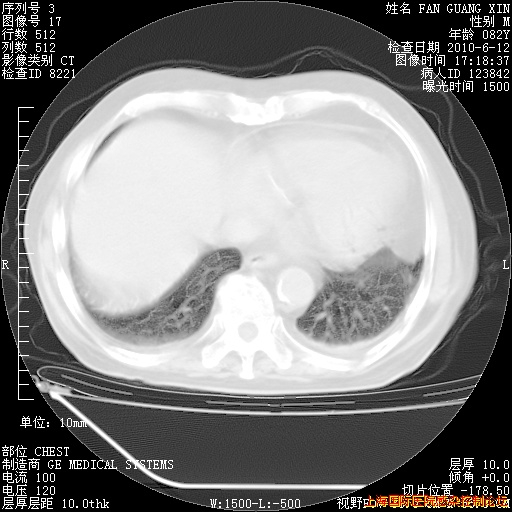

补发6月12日肺部CT肺窗

6月12日肺窗

整整相隔30天的肺部CT好像有所好转啊。甲强龙减量第3天,需要观察体温。